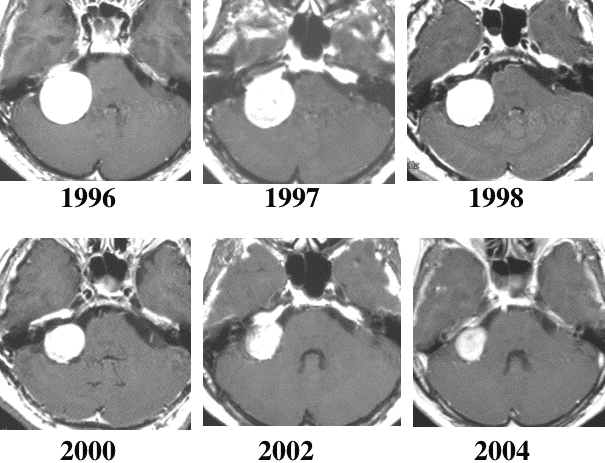

8年間観察して何もしないで小さくなってしまった大きな聴神経腫瘍です。60代半ばの女性でした。この自然退縮は,年齢が高い患者さんほど生じやすいです。また,自然退縮する前に,腫瘍ののう胞化(腫瘍の中に水たまりができる)という現象が起きることが多いです。

自然退縮(たいしゅく)とは何もしなくても腫瘍が小さくなってしまうことです。聴神経腫瘍では10%以上(文献によっては30%)にこれが起ります。ですから,なんにも治療をしなくてほっておいても何でもないことも少なからずあるのです。無理に治療をしないでまず様子を見ることも大切です。信じられない人のために例を見せましょう。